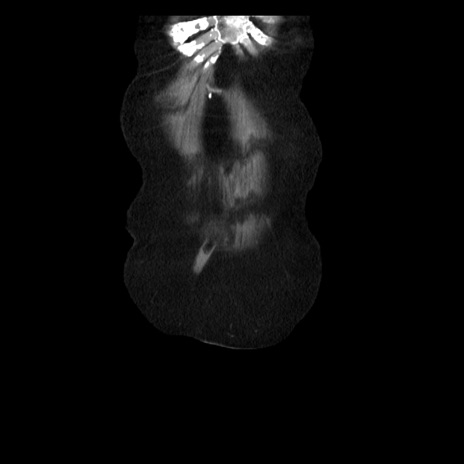

横断像